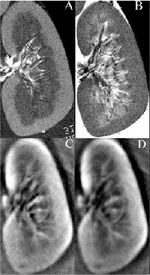

Fig. 1. Bottom: The first 3D thermoaoustic images of biologic tissue (lamb kidney). Top: MRIs of the same kidney.

Thermoacoustic imaging was originally proposed by Theodore Bowen in 1981 as a strategy for studying the absorption properties of human tissue using virtually any kind of electromagnetic radiation.[1] But Alexander Graham Bell first reported the physical principle upon which thermoacoustic imaging is based a century earlier.[2] He observed that audible sound could be created by illuminating an intermittent beam of sunlight onto a rubber sheet. Shortly after Bowen's work was published, other researchers proposed methodology for thermoacoustic imaging using microwaves.[3] In 1994 researchers used an infrared laser to produce the first thermoacoustic images of near-infrared optical absorption in a tissue-mimicking phantom, albeit in two dimensions (2D).[4] In 1995 other researchers formulated a general reconstruction algorithm by which 2D thermoacoustic images could be computed from their "projections," i.e. thermoacoustic computed tomography (TCT).[5] By 1998 researchers at Indiana University Medical Center[6] extended TCT to 3D and employed pulsed microwaves to produce the first fully three-dimensional (3D) thermoacoustic images of biologic tissue [an excised lamb kidney (Fig. 1)].[7] The following year they created the first fully 3D thermoacoustic images of cancer in the human breast, again using pulsed microwaves (Fig. 2).[8] Since that time, thermoacoustic imaging has gained widespread popularity in research institutions worldwide.[9][10][11][12][13][14][15] As of 2008, three companies were developing commercial thermoacoustic imaging systems – Seno Medical,[16] Endra, Inc.[17] and OptoSonics, Inc.[18]

Fig. 2: First 3D thermoacoustic image of breast cancer. From left to right: axial, coronal and sagittal views of the cancer (arrows).